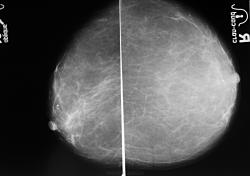

Это левая и правая (сс и обликва вместе) делал не я.

Срелочками показать не могу, справа здоровая молочная железа, а слево и есть то самое "Ифильтративное чудовище"(вся железа)

Видимо компьютер не очень хорошо передает изображение, на снимках не видно утолщенной кожи и подкожной клетчатки, только тени участков отека железы, сглаженность структурных элементов. все это видно при  сравнении со здоровой железой. Справа - вторая железа этой же  женщины?  Предлагаю для демонстации утолщение кожи за счет отека.